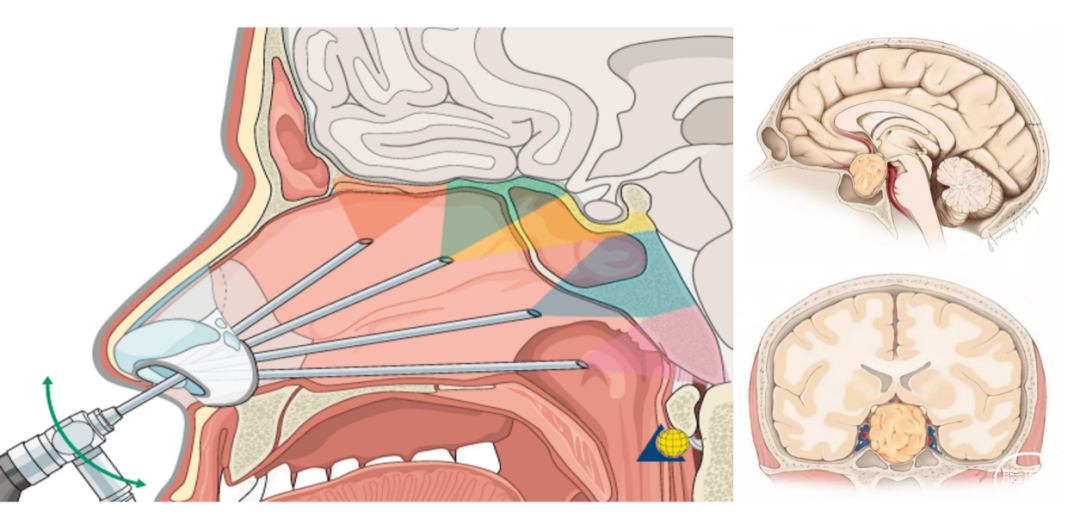

神经内镜微创手术通过鼻腔或小切口进行,避免了传统手术的大范围的手术切口,减少了手术创伤,患者术后恢复速度明显加快,此技术是我科近年来开展的院内新技术之一。垂体腺瘤、鞍区肿瘤及松果体区肿瘤位置深在,周围结构复杂,传统手术难度大、风险高,这类肿瘤特别适合利用神经内镜的抵近观察和精细操作,能够更精准地切除肿瘤,同时减少对周围正常组织的损伤。此技术在我们科已广泛应用,并取得了良好的治疗效果,为颅内肿瘤患者带来福音。